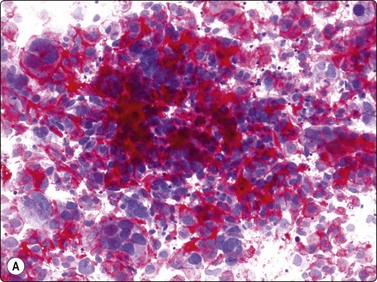

Langerhans cell histiocytosis presents as lytic and often well-defined lesions. Most cases are seen in children. The lesions may be solitary (most cases) or multiple. The long bones (femur and humerus) and the skull are the most common sites in children, and the pelvic bones and ribs in adults. The cytological pattern of Langerhans cell histiocytosis is fairly characteristic and may be diagnostic. The typical histiocytes have moderately larger and paler nuclei than those seen in common inflammatory processes. Generally reniform, the nuclei have a distinct irregular and folded outline (Fig. 16.10A). Coffee-bean nuclei has been reported to be typical of this lesion (Fig. 16.10B). The chromatin is entirely bland and nucleoli small. The cytoplasm is abundant and pale and has fairly well-defined borders. It is often vacuolated. In exceptional cases the Langerhans cells may show signs of phagocytosis. Multinucleated cells of similar type are commonly present. These can be quite large and may resemble osteoclasts in wet-fixed smears.

image image

Fig. 16.10 Langerhans cell histiocytosis (eosinophilic granuloma)

(A) Lytic bone lesion, many histiocytes with irregular reniform pale nuclei, some eosinophils (H&E, IP); (B) Coffee-bean nuclei have been reported to be typical of this lesion (H&E, HP, Oil)